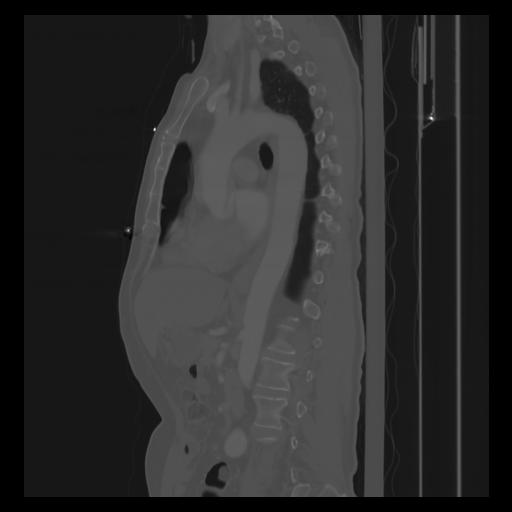

30 CUERPO,CE,Sagittal,3.000,CUERPO,Sagittal,